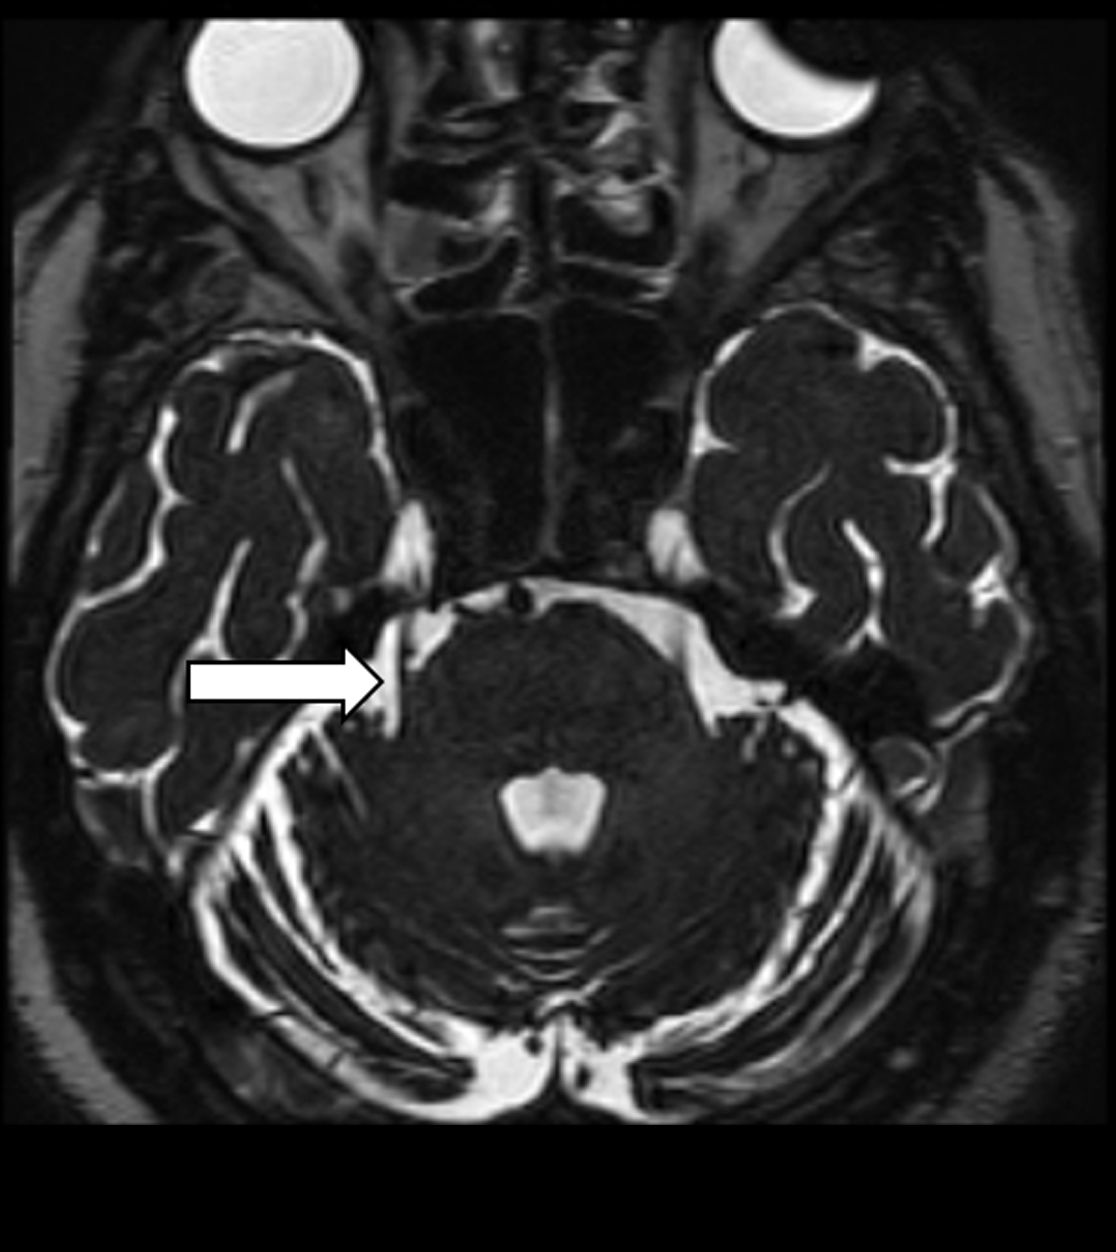

Liegt bei einer Trigeminusneuralgie eine Gefäßschlinge vor, welche den Trigeminusnerv berührt, kann bei unzureichender Linderung durch eine medikamentöse Therapie ggf. durch eine operative Lösung von Nerv und Gefäß eine Schmerzreduktion erreicht werden. Hierfür wird der Trigeminusnerv an seiner Eintrittsstelle zum Hirnstamm aufgesucht und durch z.B. ein Teflon-Stück vom Gefäß getrennt.

Gefäß-Nerven-Kontakt im Bereich des Nervus trigeminus (Pfeil)

Status nach mikrovaskulärer Dekompression über einen Zugang hinter dem Ohr (Pfeil)